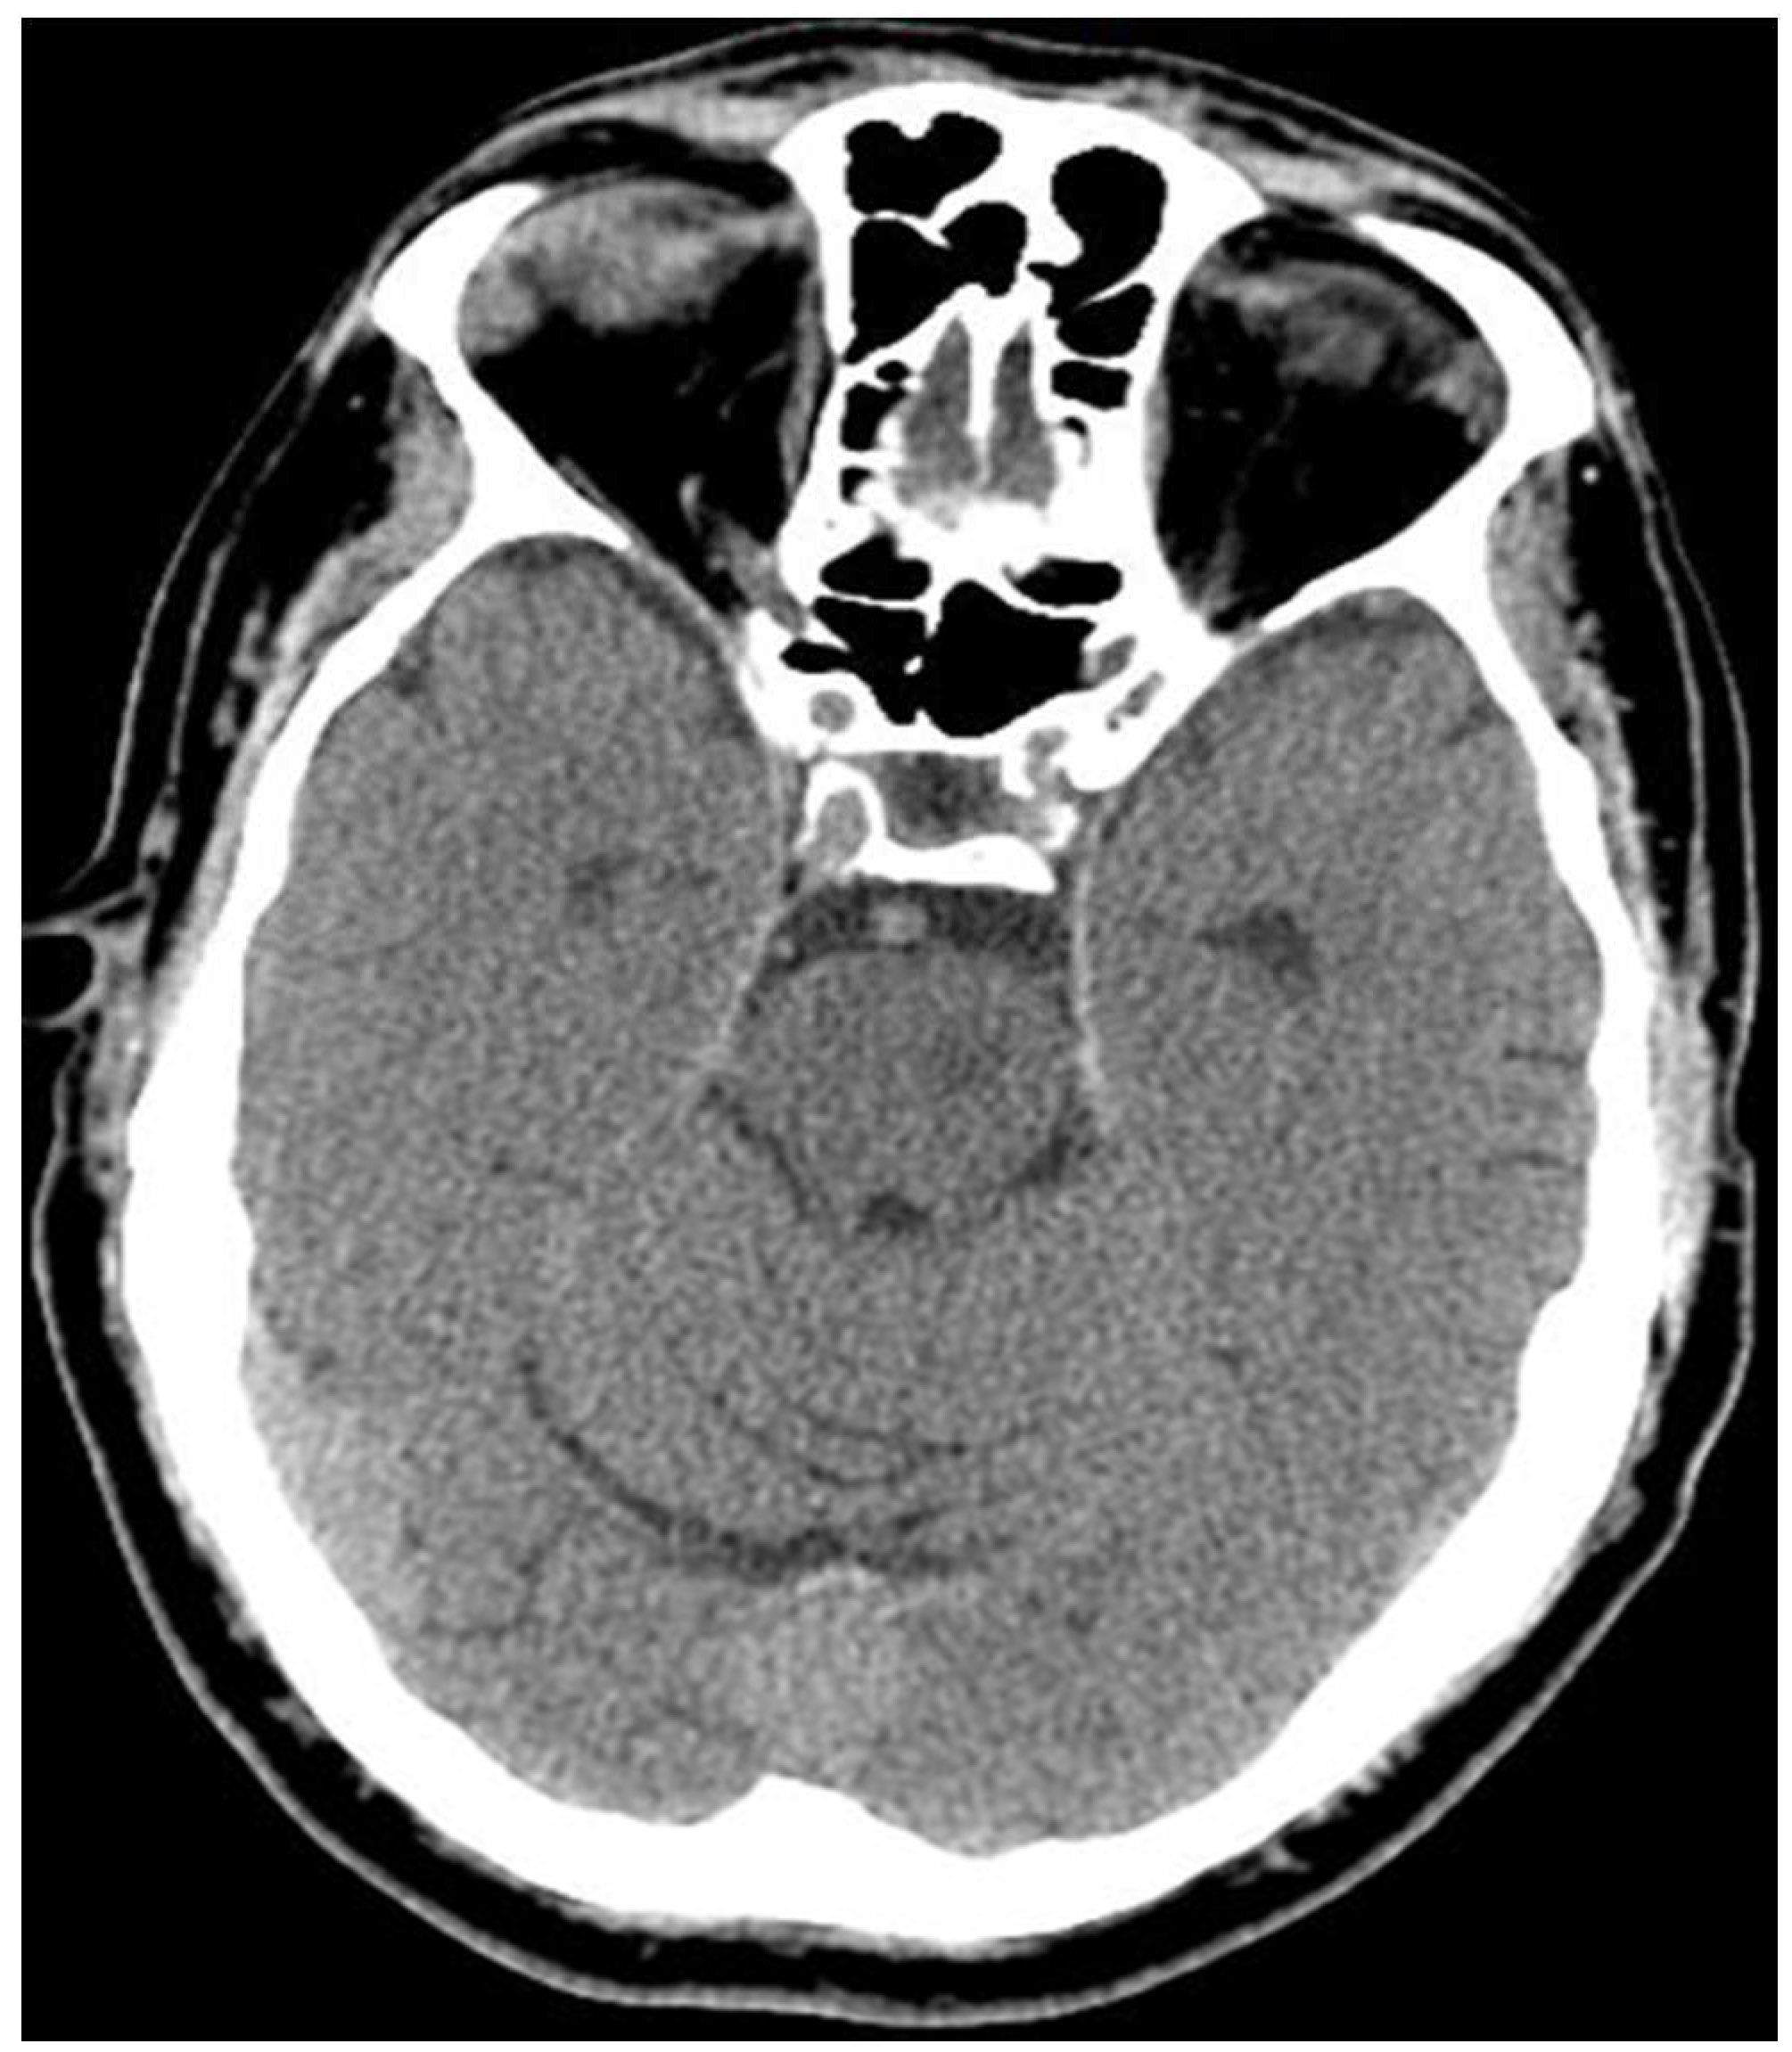

Case 1: A 61-year-old man with complaints of left-sided hemiplegia for 4 hours.

He was presented to the clinic with a loss of consciousness. The CT scan shows a large hypodensity involving the entire right temporal lobe, extending superiorly to the right parietal lobe.

ASPECTS MCA- 6, ASPECTS PCA- 10

The patient was admitted to the ICU, intubated for 2 weeks with no improvement and expired on day 17 of admission.

Figure 1. NCCT of case 1.